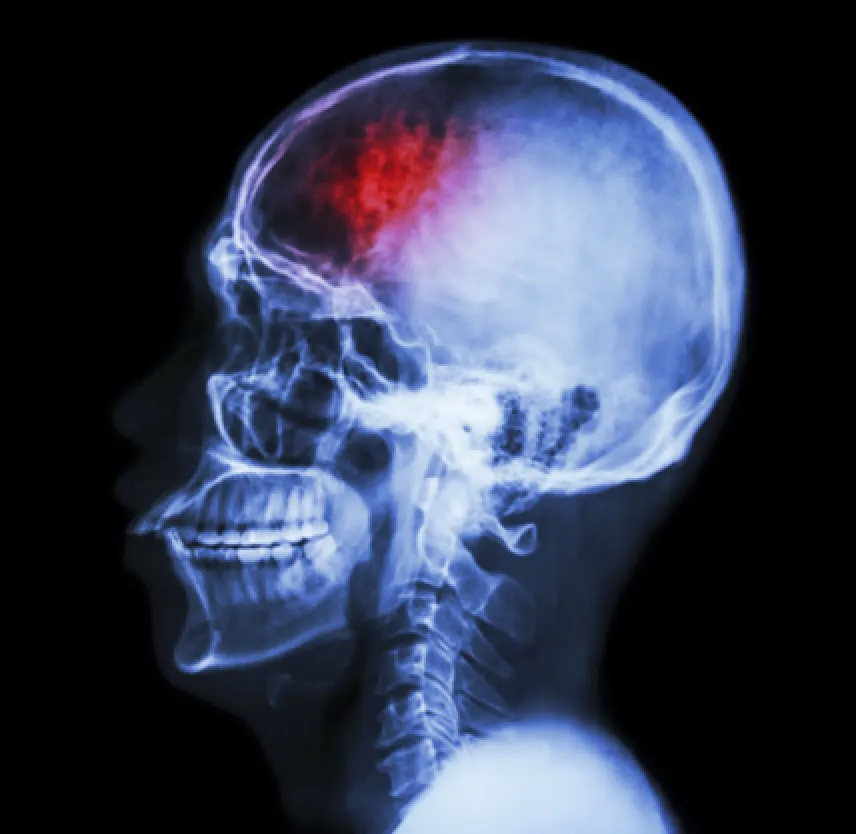

Suffered a brain injury? Hire #TheMcAllenPersonalInjuryLawyer

When you sustain a head injury, a host of symptoms can come into play. When you suffer a brain injury, those symptoms are more pronounced and more severe.

Some of the more common major signs of a brain injury following a car wreck:

Brain injuries require medical treatment. Doctors commonly use MRIs and CT scans to see if there is permanent damage or bleeding in the brain. Mild to moderate brain injuries are treated conservatively with medication and rest. Diuretics, anti-inflammation medicines, anti-seizure drugs and pain medication are used to alleviate symptoms. If there is bleeding in the brain or a skull fracture, surgery may be a life- saving option that doctors use for treatment.